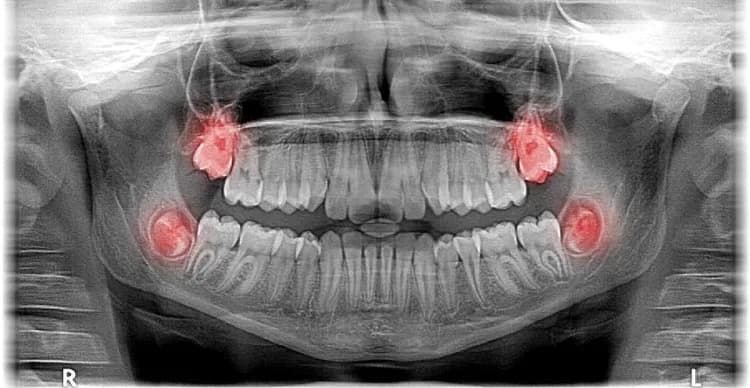

Czy ósemki rosną na górze? Odkryj prawdę o zębach mądrości

Czy ósemki rosną na górze? Dowiedz się, gdzie wyrastają zęby mądrości i jakie mogą wystąpić problemy podczas ich pojawiania się.

Czy ósemki rosną na górze? Odkryj prawdę o zębach mądrości

Czy ósemki rosną na górze? Dowiedz się, gdzie wyrastają zęby mądrości i jakie mogą wystąpić problemy podczas ich pojawiania się.